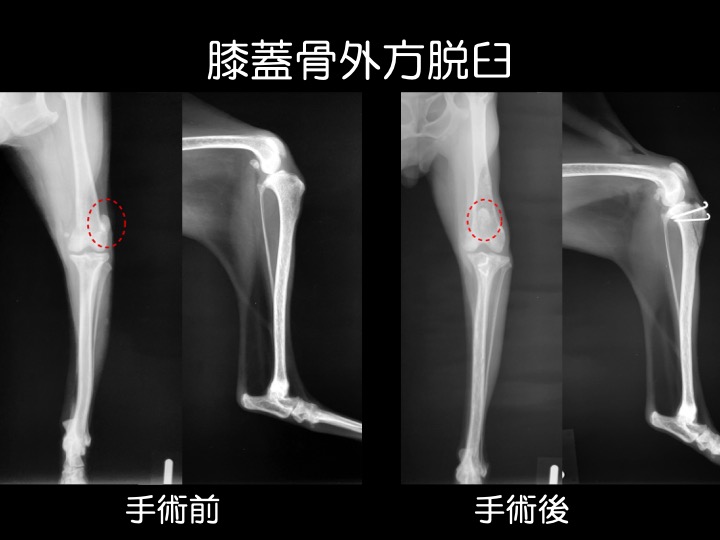

・内方脱臼と同様に外傷が原因で脱臼することもありますが、多くは先天性で成長期の異常として見つかります。中等症以上の場合には、手術が検討されます。

・写真のワンちゃんのように、経過が長い子は、痛みから足を着かなくなってしまい、足全体の筋肉が徐々に痩せていってしまいます。

・外方脱臼は内方脱臼よりも痛みが強く出る傾向があり、跛行などの症状も顕著です。

※ 大型犬に見られる外方脱臼は、小型犬のそれとは異なる病態と考えられており、治療にあたっては専門的な知識や経験が必要です。高度医療施設への受診を推奨しています。